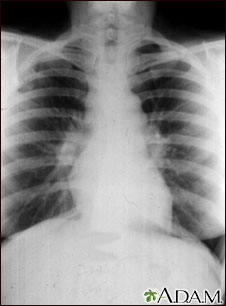

Different imaging tests may help diagnose sarcoidosis:

- Chest x-ray to see if the lungs are involved or lymph nodes are enlarged